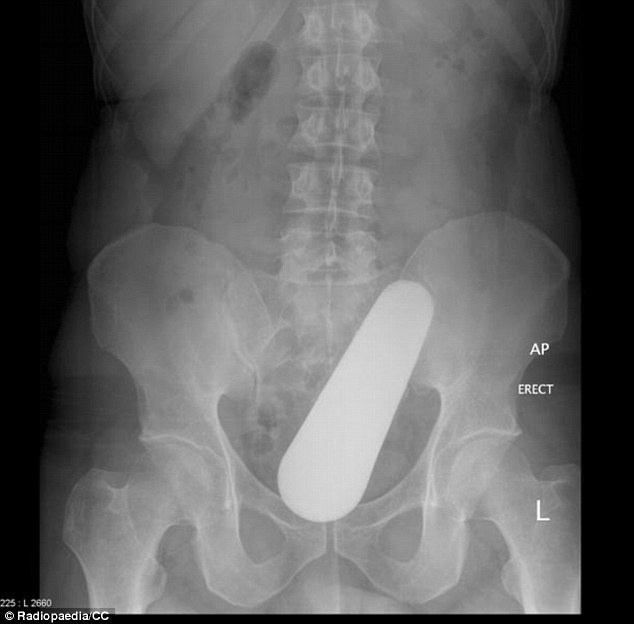

| Chiếc chày nhỏ chui vào trực tràng của một người đàn ông qua hậu môn khi anh đang nấu món ăn Malaysia. |